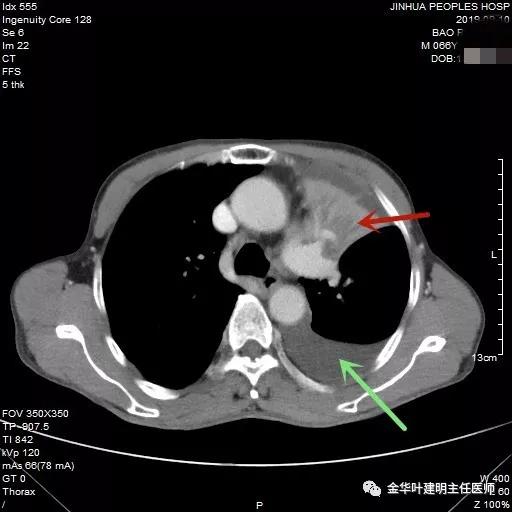

红色箭头示不张的肺,绿色示胸水

肿瘤与左肺动脉主干关系密切